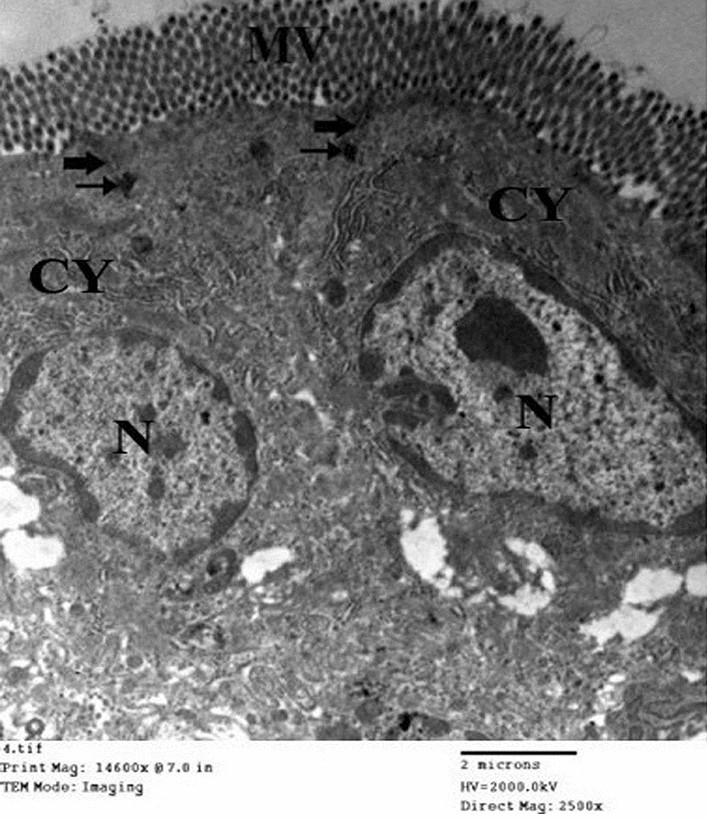

Figure 8

Electron micrograph of an ultrathin section in the small intestine of drug granules prepared on using 15% span 60 (Mic. Mag × 2500).